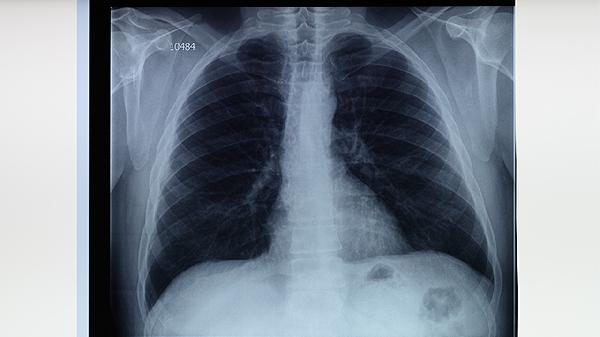

治疗期间每月需进行痰涂片检查、胸部X线复查及肝肾功能检测。痰菌转阴后仍需持续监测,直至疗程结束。复查可评估治疗效果,及时发现药物性肝损伤等并发症。患者应保留所有检查报告,便于医生动态调整治疗方案。